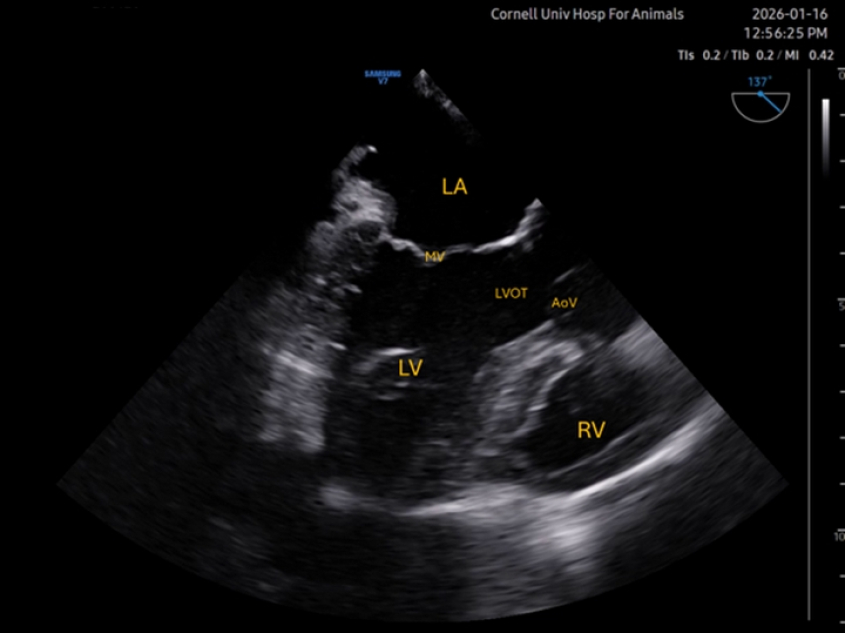

Mid-esophageal long axis (ME LAX)

Rotation of the omniplane to approximately 100° brings the left-ventricular outflow tract (LVOT) and aortic valve (AoV) into view. Color Doppler can be applied over the aortic and mitral valves. The view also allows to assess contractility of different walls than those observed with the ME 4C. In the clip below, insufficiency of both valves can be observed concurrently. In this case, mitral insufficiency was naturally occurring, but the aortic reflux was secondary to placement of a ventricular catheter in our research laboratory.